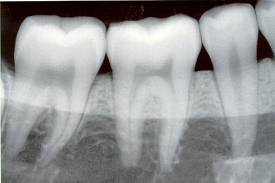

Adicionalmente, su dentista tomará radiografías de diagnóstico para revelar otros problemas ocultos. Se toma radiografías Bitewing cada 12 meses para detectar caries entre los dientes. Radiografías periapicales para una observación minuciosa de las raíces de los dientes así como de las estructuras adyacentes. Cada 3-5 años se toma una radiografía panorámica, la que involucra el uso de una máquina que gira alrededor de la cabeza, para examinar todo el maxilar, por si existieran problemas.